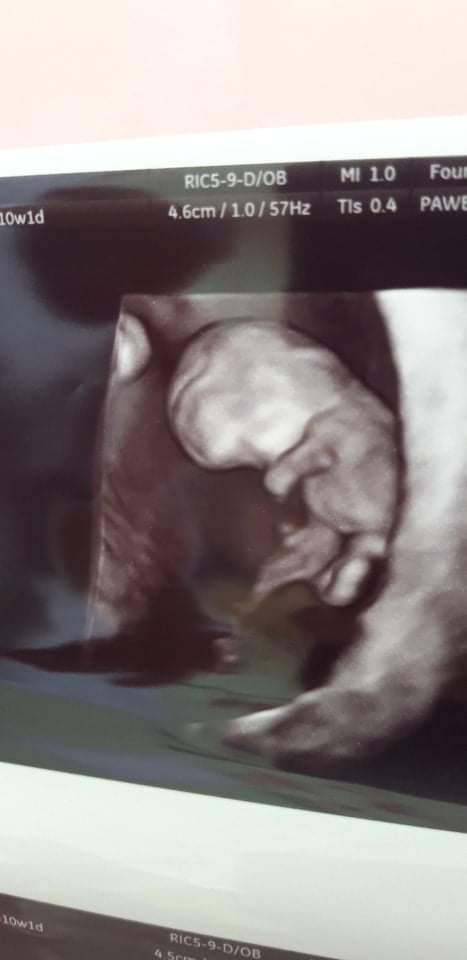

Wczoraj miałam drugą wizytę, wszystko jest super, wyniki badań w porządku, moje Cudeńko zdrowo rośnie🙂😊

Z Om 10tydzień i 1 dzień, a z USG 9tydzień i 4 dni, maluszek ma 2,6cm🙂

Załączniki

• received_1201400904003808.jpeg

received_1201400904003808.jpeg

21,3 KB · Wyświetleń: 116